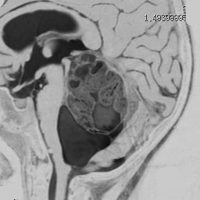

12歳の少女の小脳虫部と右半球深部白質の間にできた毛様細胞性星細胞腫 pilocytic astrocytoma です。軽い体幹失調がありました。のう胞壁の大部分には腫瘍はありませんが,一部に腫瘍壁があります。必ずしも境界は明瞭ではなく,小脳虫部の上内側面に広範囲に接着しています。年長児の毛様細胞性星細胞腫は,Rosental fiber, eosinophilic granular bodyが多く見られ,硬く,小脳脳組織に食い込み,簡単に剥離摘出できるものではありません。脳組織と切開切断するように切り落とさなければ全摘できないものです。

この腫瘍を後頭下開頭で摘出しようとすれば,小脳虫部と右小脳半球の間をかなり長く縦切開しなければなりません。テント直下から小脳上面をたどっても腫瘍の上端は見えても摘出は不可能です。ですから,必然的にアプローチは後頭開頭経テント法 occipital transtentorial approachとなります。